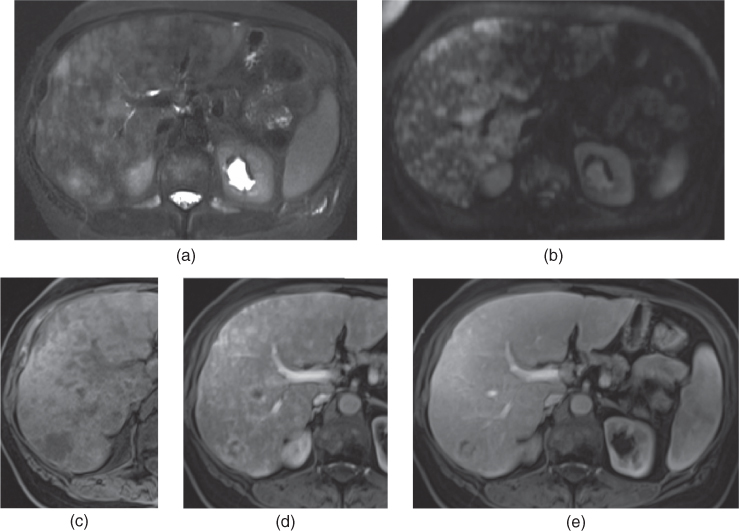

From www.semanticscholar.org

Figure 1 from Imaging of hepatic metastases. Semantic Scholar Does Liver Mets Cause Pain For example, if the liver cancer spreads to the bones, it may cause bone fractures. Symptoms of secondary liver cancer (liver metastases) can include: Many of these symptoms are very common and can be caused by different conditions. Loss of appetite, weight loss, feeling sick, tiredness, aching and high. In most cases, there is no way to cure liver metastases.. Does Liver Mets Cause Pain.